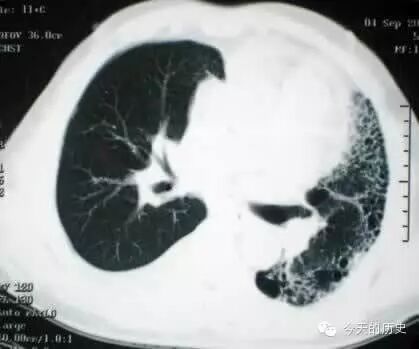

1986年10月28日,心肺同时移植首次在西班牙完成。

198610月28,西班牙潘普洛纳市纳瓦拉大学医院成功地进行了一次心脏和肺脏同时移植手术。这一手术在西班牙是第一次。接受心肺植入手术的是十三岁的女孩阿尔穆德纳-加尔韦斯,她因双肺纤维性病变,呼吸十分困难。这家医院心血管外科专家二十七日午夜开始对女孩施行移植手术,手术复杂艰难,持续到二十八日凌晨四点。据手术医生说,手术后女孩感觉良好。植入女孩的心脏和肺脏取自一位十一岁的男孩,他是不幸因脑颅创伤死亡的。据报道,截止一九八五年,全世界共作过一百零八例心肺同时移植手术,其中绝大部分是在美国和英国进行的。美国是世界上第一个心肺同时移植手术获得成功的国家。